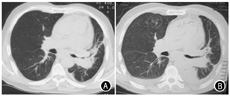

患者于2019年7—8月行一线GP方案(吉西他滨1.6 g第1天和第8天,顺铂40 mg,第1~3天)化疗2个周期,出现3级化疗相关消化道不良反应,化疗后未复查CT评估疗效。2020年6月患者出现腹胀、嗜睡、恶心呕吐。复查胸部CT示,左肺门软组织影(长径为90.8 mm)及右肺下叶结节(长径为23.8 mm),提示肺内病灶增大,新发右肺转移,考虑病情进展,经患者及家属商议,决定行免疫治疗。2020年6月12日给予信迪利单抗200 mg静脉滴注,同时口服安罗替尼12 mg(第1~14天)行抗血管生成靶向治疗。2020年6月28日患者因持续恶心呕吐再次入院,肝功能示,谷氨酸氨基转移酶(alanine aminotransferase, ALT)为542 U/L、天门冬氨酸氨基转移酶(aspartate transaminase, AST)为475 U/L、总胆红素(total bilirubin, TBIL)为33.61 mmol/L、直接胆红素(direct bilirubin, DBIL)为18.79 mmol/L。给予复方甘草酸苷、异甘草酸镁保肝治疗。6月29日复查肝功示,ALT为712 U/L,AST为695 U/L,TBIL为31.9 mmol/L,DBIL为19.06 mmol/L,自身抗体谱均为阴性,甲型、乙型、丙型肝炎病毒均为阴性。复查胸腹部CT示,左肺下叶占位,纵隔内多发肿大淋巴结,少量心包积液,双侧少量胸腔积液,脂肪肝,少量腹水。考虑诊断为免疫检查点抑制剂(immune checkpoint inhibitors, ICIs)相关肝损伤G3级。2020年6月29日给予甲强龙80 mg/d静脉滴注,同时予保肝退黄治疗。6月30日复查肝功示,ALT为634 U/L、AST为393 U/L、TBIL为26.25 mmol/L、DBIL为16.78 mmol/L。考虑治疗有效,继续予甲强龙80 mg/d静脉滴注。7月4日复查肝功示,ALT为249 U/L、AST为58 U/L、TBIL为28.52 mmol/L、DBIL为20.6 mmol/L,肝功下降至G2级,于7月5日甲强龙减量至60 mg/d。7月7日复查肝功示,ALT为148 U/L,AST为40 U/L,TBIL为45.57 mmol/L,DBIL为32.62 mmol/L,继续予激素治疗,患者喘憋气短加重,咳吐腥臭痰。7月10日复查肝功示,ALT为435 U/L,AST为245 U/L,TBIL为95.89 mmol/L,DBIL为67.62 mmol/L,提示肝损伤复发,建议患者完善肝穿刺活检明确病理情况,患者及家属拒绝,决定接受临终关怀护理而未进行治疗。患者于2020年7月12日死亡。患者胸部CT情况见图1。